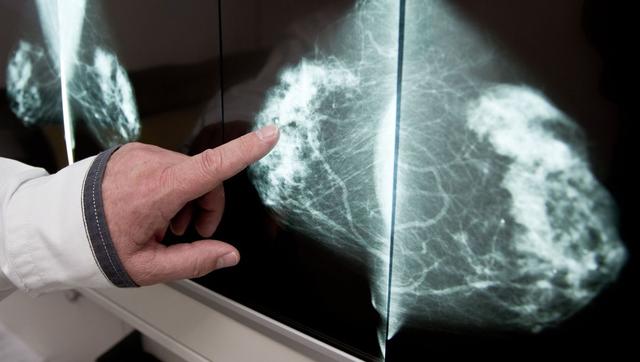

Der Ultraschall der Brust wird oft als Ergänzung zur Mammographie eingesetzt, insbesondere wenn Ärzte die Röntgenbilder nicht sicher beurteilen können. Während die Mammografie die beste Methode ist, um Veränderungen in der Brust festzustellen, kann der Ultraschall wertvolle Zusatzinformationen liefern.

Die Bedeutung von Ultraschalluntersuchungen nach einer Mammographie liegt darin, dass sie zusätzliche Informationen liefern können, wenn die Mammografie-Röntgenbilder nicht eindeutig sind. In bestimmten Fällen können Ärzte und Ärztinnen durch den Ultraschall besser beurteilen, ob es sich bei verdächtigen Befunden um flüssigkeitsgefüllte Zysten oder um Gewebeknoten handelt. Besonders bei Frauen mit bindegewebsreicher Brust, wie jungen Frauen vor den Wechseljahren, ist der Ultraschall aussagekräftiger als die Auswertung von Mammografie-Aufnahmen.

Es ist wichtig zu beachten, dass der Ultraschall alleine meist nicht ausreicht, um Brustkrebs sicher nachzuweisen. Die Mammografie bleibt die beste Methode zur Feststellung von Veränderungen in der Brust. Der Ultraschall kann jedoch wertvolle Zusatzinformationen liefern und bei unklaren Befunden helfen, eine Biopsie zu vermeiden.